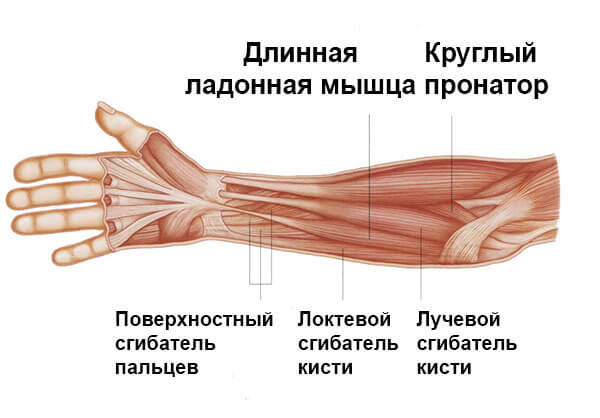

Анатомия мышцы Palmaris Longus